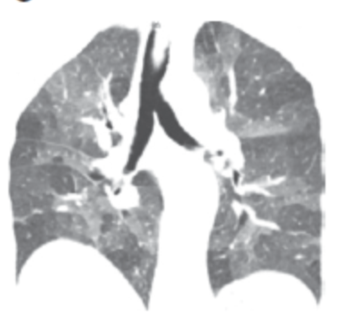

从这张图片上,我们看到两种密度,高密度的是磨玻璃影,而低密度可能是正常的肺组织,也可以是由于小气道疾病引起的。

这是另外一个例子,双肺有斑片状的磨玻璃影,同时看到了有少量囊腔,还看到了正常密度的肺脏,双下肺靠近胸膜的地方有少量实变。